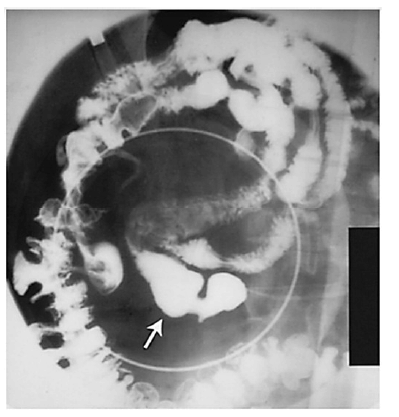

Um paciente do sexo masculino, de 38 anos de idade, assintomático, chega ao consultório médico de um cirurgião em razão de uma alteração em exame de imagem. O paciente é previamente hígido. Refere praticar atividade física, que consiste em corridas e academia quatro vezes por semana, no total. Nega uso contínuo de medicações, tabagismo, alcoolismo e uso de drogas. Além disso, relata não ter tido alergias medicamentosas nem ter feito cirurgias prévias. Nega dor abdominal, náuseas, vômitos e outros sintomas. Declara não ter ocorrido emagrecimento recente. Ao exame físico, o paciente está em bom estado geral, lúcido e orientado. Os resultados de seus exames são: PA = 120 mmHg x 80 mmHg, FC = 80 bpm, Sat. de 98% em ar ambiente. Abdome: flácido, depressível, indolor. Sem massas palpáveis ou visceromegalias. O exame alterado foi de raios X de abdome com contraste baritado, que está representado na figura.

De acordo com o caso clínico exposto e com os conhecimentos relacionados à imagem, julgue os itens a seguir.